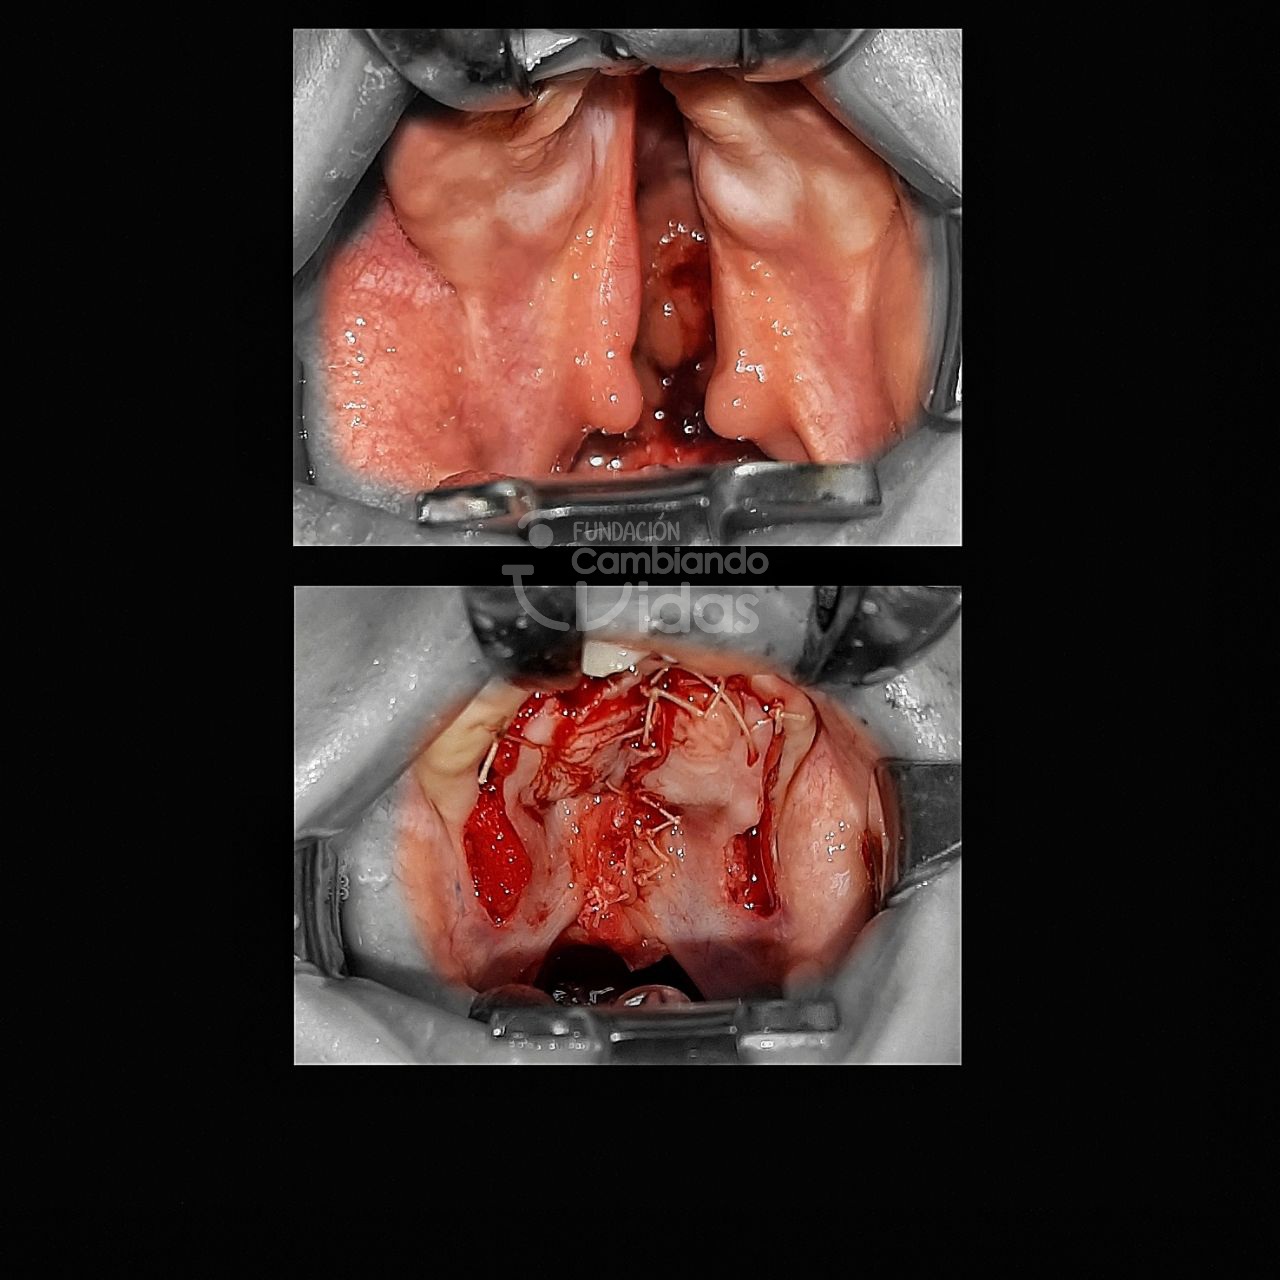

Paula Díaz

Intervención Quirurgica: Rinoqueiloplastia Secundaria y Palatoplastia Primaria